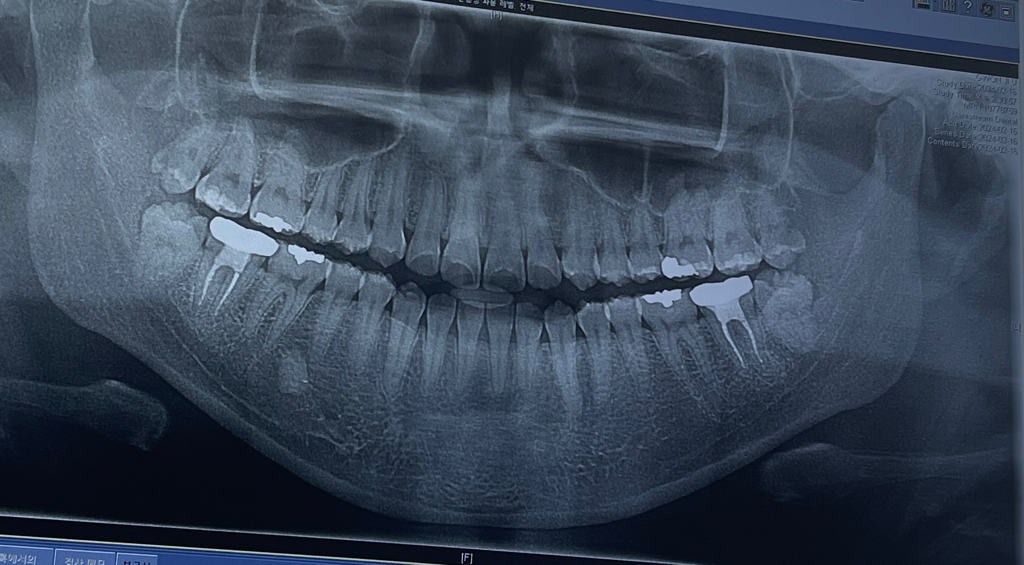

제가 곧 사랑니를 빼는데 지금 아픈쪽은 오른쪽 위 사랑니가 썩어서 엄청 아파요. 근데 병원가니까 사랑니 뺄때 주의사항에 빼고난 후 살? 잇몸 구멍이 안채워지거나 이가 시리거나 턱,얼굴 마비가되거나 등등 이런 무서운 부작용이 있던데 흔한 부작용인가요?ㅠㅠ 의사선생님께서 설명을 무섭게 해주셔서 빼야할지 빼지 말아야할지 모르겠어요....

그리고 제 사랑니는 신경에 많이 닿아있나요? 위험할까요 ㅠㅠ 매복사랑니라서 잇몸을 째야한다던데....🥺🥺🥺🥺🥺

사진은 왼쪽이 오른쪽 이빨, 오른쪽이 왼쪽 이빨 입니다...

말씀하신 부작용은 가능성이 없진 않으나 거의 없습니다. 가까운 편이지만 경험많은 치과에서 하시면 잘뽑을 수 있습니다.

저정도 사랑니 발치는 크게 어려운 난이도의 발치를 아니신거 같습니다. 혹시라도불안하시면 대학병원 구강외과를 가셔서 발치를 하시면될것같습니다.

동의서 내용은 가능성의 부분입니다 발생가능한 부작용을 모두 설명할 의무가 있어서 설명해주는 것이고 발생 가능성은 낮습니다

위 사랑니는 어렵지 않게 뺄 수 있을 것으로 보이고 아래 사랑니는 뼈에 걸려있기 때문에 잇몸 절개하고 뼈를 약간 삭제하고 뽑는 수술발치를 하게 됩니다 아래턱 신경과 근접한 것은 맞습니다 발치 전 정확한 확인을 위해 ct를 찍어보면 좋을 것 같습니다